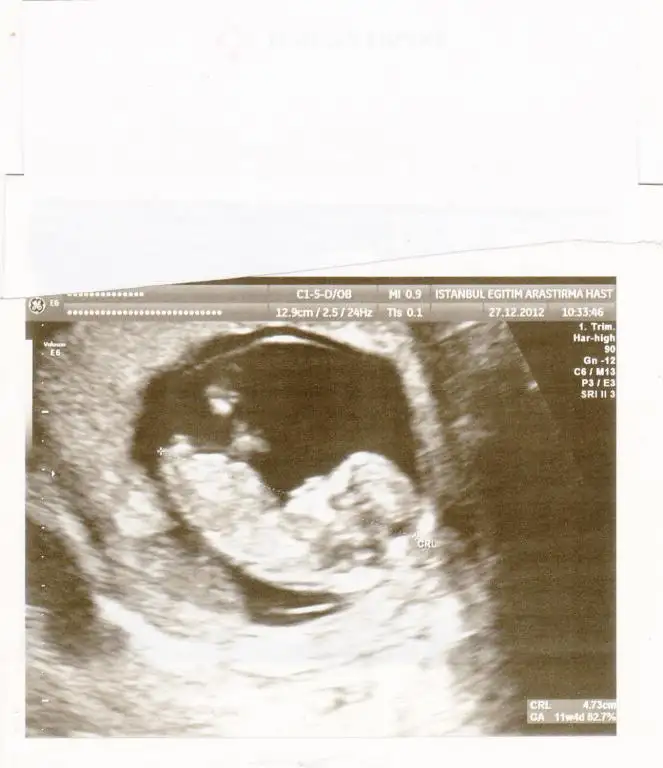

dr soylemeden siz gorun genital nub teorisi ( bebegin cinsiyeti)

kızlar bu da benimkinin son resmi :)) doktor erkek olabilir belki dedi orası çok karışık ama net bişey söyleyemem dedi bide siz bakın bakalım benim de içime hep kız doğuyordu çini rusu musu hepsinde de kız çıkıyordu bilemedim bende şimdi :))

aslinda resmin tahmin icin uygun degil popsu asagida olmali tahmin icin ama bana cok parallel geldi, eger 13 haftada gittiysen bu nub kiz nubu:) ama onceden gittiysen aci degisebilir sonradan.

pardon alinti yapinca resmini daha net gordum aksine yukari dogru aci var sanki ama iste pozisyonu yanlis, pozisyona gore nubun gorunusu degisiyor.